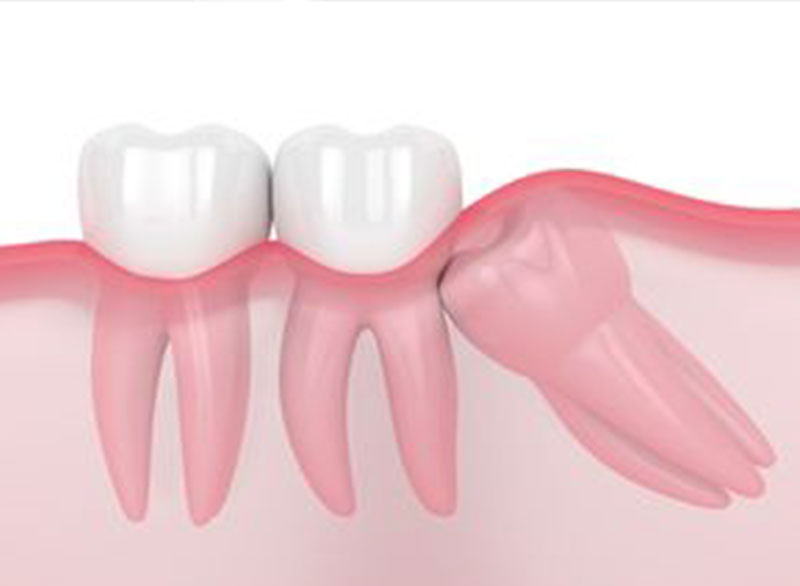

Wisdom tooth that needs to be surgically removed, in most cases they are painful and need to be removed.